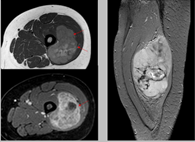

Se usa una amplia gama de técnicas de adquisición de imágenes para poder ver dentro del cuerpo y determinar el alcance de un sarcoma óseo y establecer la presencia o ausencia de enfermedad metastásica distante.

2. Resonancia magnética

3. TAC contrastado

Pruebas de imágen

Las imágenes más representativas o más comunes son:

3. Tomografía Computarizada

5. Resonancia Magnética